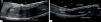

Ultrasound imaging can be used as a noninvasive confirmatory test (Figure 5). It allows clear visualization of nail components in real time and effectively rules out tumor entities and hidden complications. Important sonographic criteria for diagnosing retronychia are the presence of more than 2 overlapping nail plates, decreased distance between the origin of the nail plates and the base of the distal phalanx (level of the distal interphalangeal joint compared with the contralateral digit), decreased echogenicity, and increased blood flow in the dermis of the posterior nail fold and proximal nail bed. 7,8,14,16

Ultrasound longitudinal view of the hallux distal phalanx dorsal aspect. A - Retronychia, showing 3 overlapping nail plates* (PNF: proximal nail fold). B - Normal nail unit in the contralateral hallux, (PNF: proximal nail fold; DNF: distal nail fold; * dorsal and ventral nail plates; + inter-plate space)